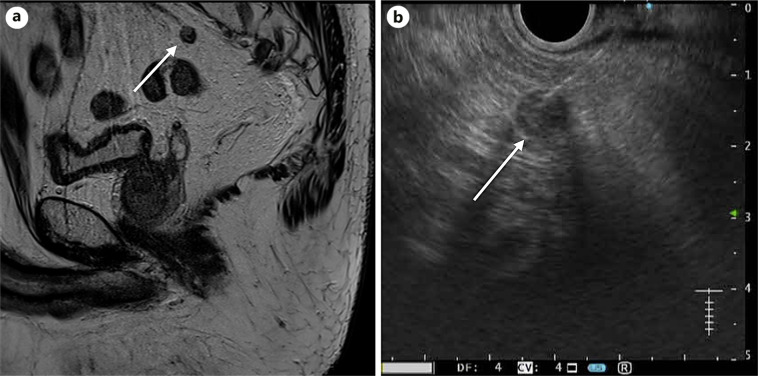

Case presentations: We report 8 cases of suspected locoregional tumor growth (LRTG) on MRI: adjacent or in the rectal wall, within the mesorectal fascia, high presacral region, and obturator foramen. MRI images were studied thoroughly before and during EUS to identify the target lesion using rectal EUS-FNA. Patients were prepared using an enema. The procedure was performed on an outpatient basis without conscious sedation. FNA was performed using a 25G needle. The patient received a 3-day course of ciprofloxacin after the procedure to prevent infection of the perirectal space. Identification of the target was the most difficult part of EUS but was successful in all cases. FNA revealed adenocarcinoma in 7 cases. Five cases were confirmed by TME results: 1 patient died before the operation, and 1 patient was treated with CRT. One patient with a suspected node in the obturator foramen was free of tumors on FNA. The TME resection specimen contained 31 lymph nodes without metastasis. All procedures were well tolerated, and no complications were observed.

Abstract Image